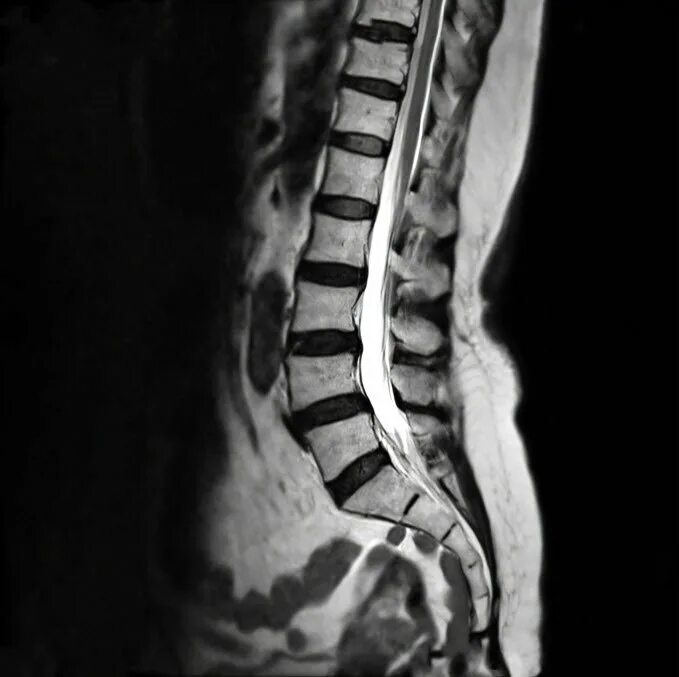

Метастазы в поясничном позвоночнике